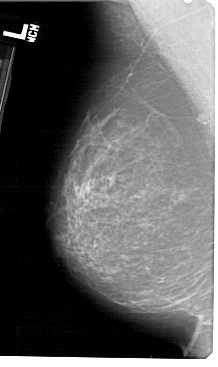

A_1418_1.LEFT_MLO

LEFT_MLO LINES 5491 PIXELS_PER_LINE 3256 BITS_PER_PIXEL 12 RESOLUTION 43.5 NON_OVERLAY

FILE: A_1418_1.RIGHT_MLO.OVERLAY

TOTAL_ABNORMALITIES 1

ABNORMALITY 1

LESION_TYPE MASS SHAPE LOBULATED MARGINS CIRCUMSCRIBED

ASSESSMENT 4

SUBTLETY 4

PATHOLOGY BENIGN